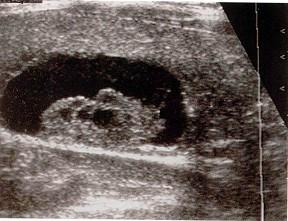

问题 发现一侧乳房无痛性肿块3天,腋窝及颈部可触及数个黄豆大包块,乳腺超声声像图如上,最可能的诊断是?(?)

选项 A.乳头状导管癌 B.髓样癌 C.乳腺淋巴瘤 D.乳腺囊性增生 E.以上都不是

答案 A